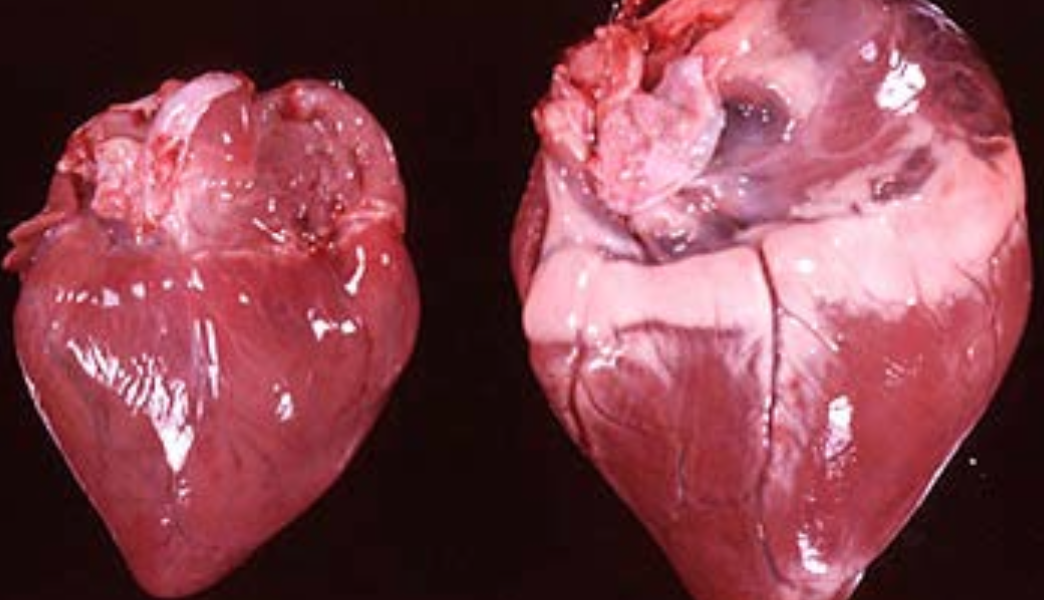

Concentric Hypertrophy

growth of a hollow organ without overall enlargement, in which the walls of the organ are thickened and its capacity or volume is diminished.

Hypertrophic cardiomyopathy (HCM) is common in ____________.

Hypertrophic cardiomyopathy (HCM) is common in Main Coon Cats.

Hypertrophic cardiomyopthy (HCM) in cats is due to a mutation in the____________.

Hypertrophic cardiomyopthy (HCM) in cats is due to a mutation in the MYBPC3 gene.

Inherited autosomal dominant

Adaptation Response

(Normal = Left)

Atrophy